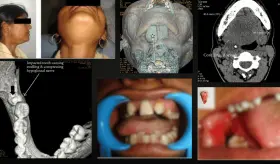

La evaluación odontológica reveló múltiples caries, ausencia de piezas dentales y hallazgos faciales críticos como la pérdida completa de la columela y destrucción casi total del tabique nasal.

Un inusual caso de malformación vascular mandibular (AVM) en una gestante de 39 semanas derivó en una hemorragia potencialmente mortal y parto por cesárea de emergencia.